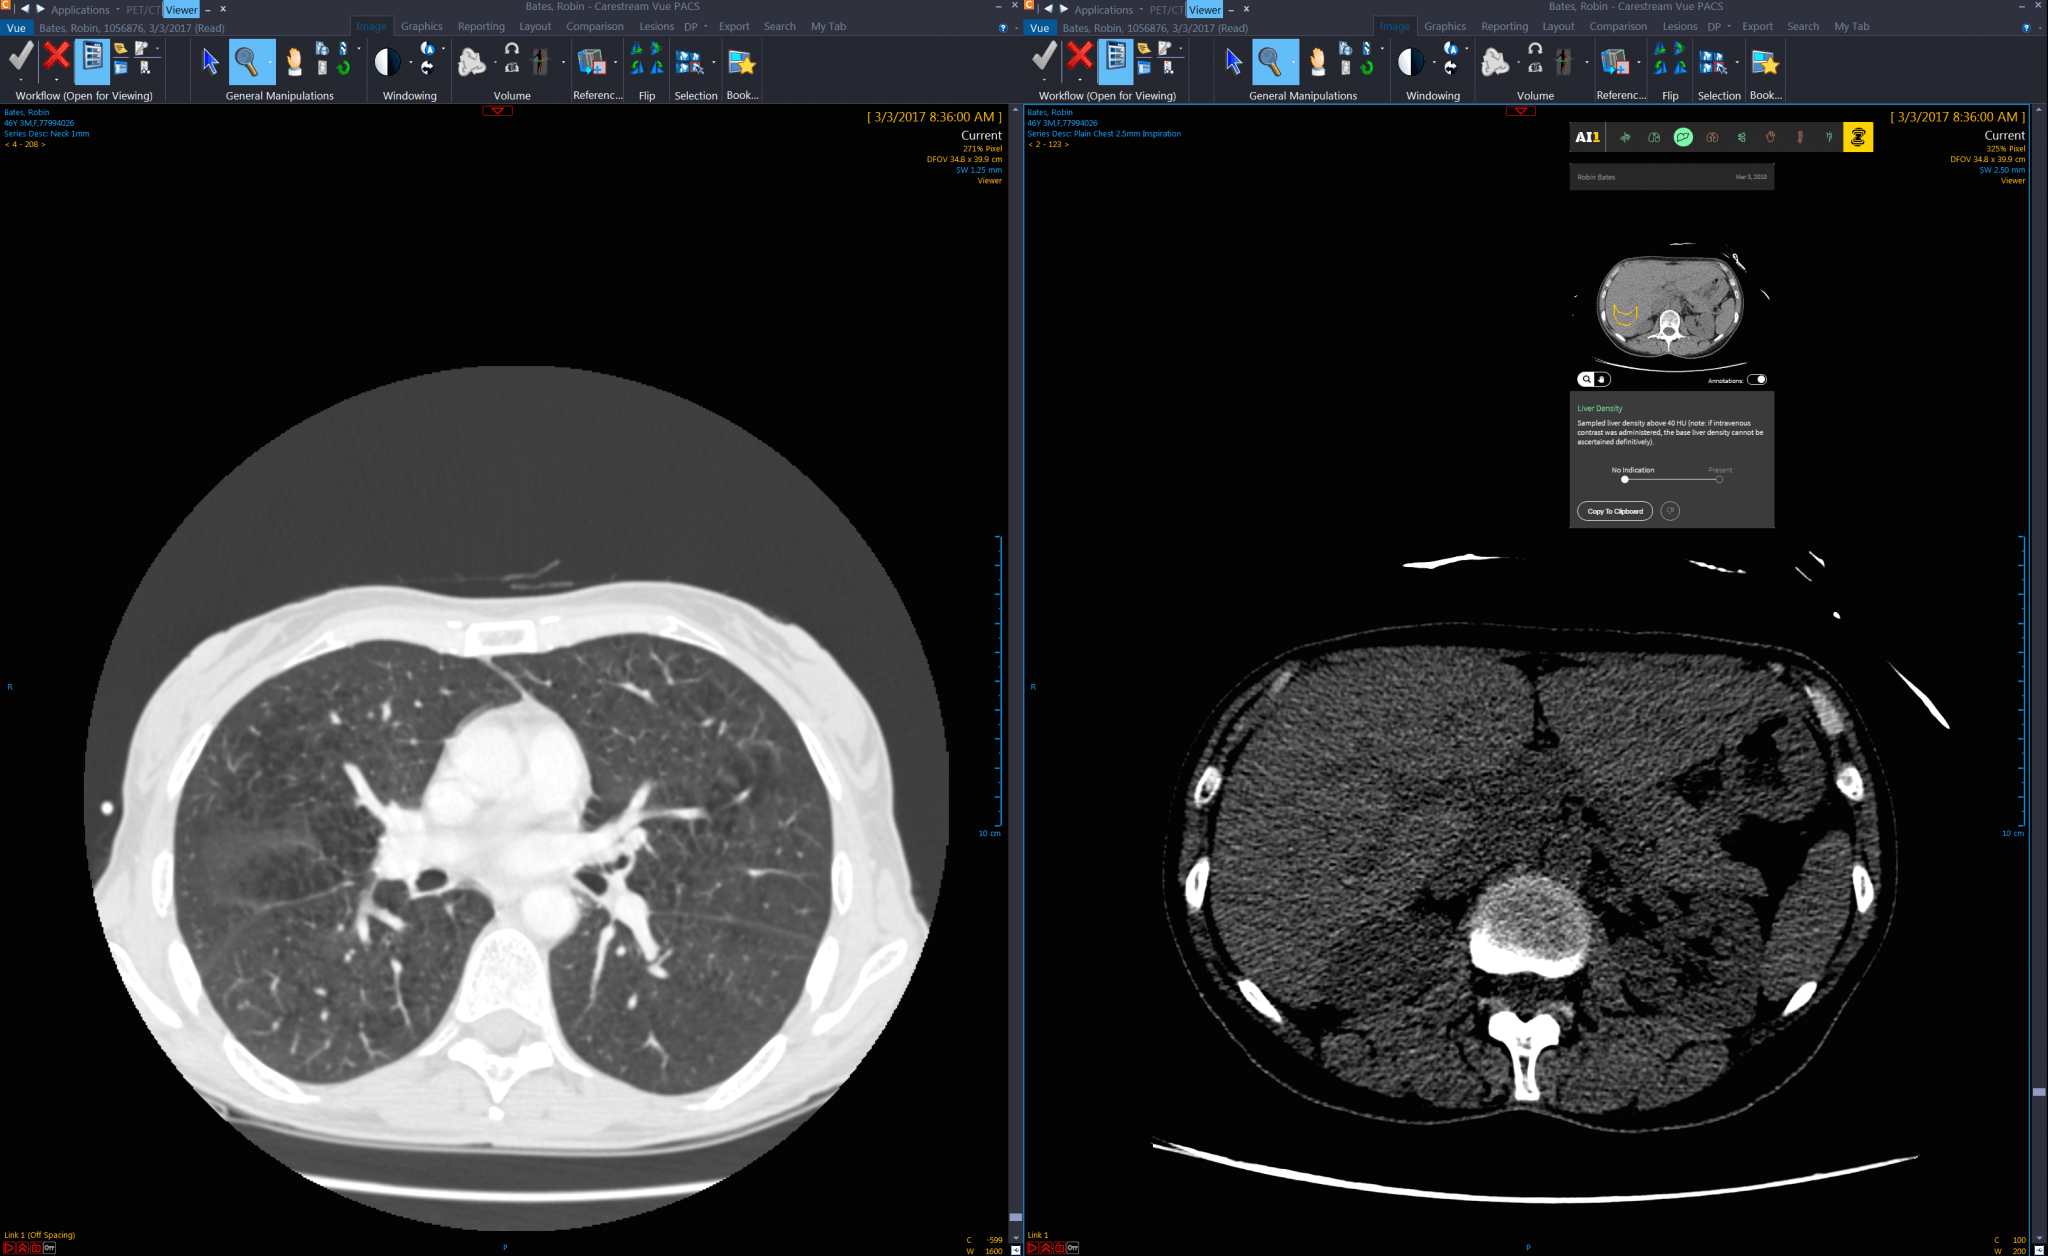

What precisely does Zebra’s algorithm do? It relies on images from x-rays and CT scans, which are both radiation-based images that create a view of the internal parts of a body, with shades of gray depicting muscles and fat, and white showing bones and metal. X-rays are the single images from a scan, and CT scans are a series of X-ray scans that together make up a three-dimensional image.

Since the 2000s, these images have been increasingly digitized, which allowed for faster, more efficient, and cheaper methods of analysis. The digital copies allowed researchers to use collections of the scans more easily for research purposes, especially for machine learning purposes. Zebra builds on this digital foundation and the research into how to use it for algorithm development.

To date Zebra’s algorithms use large amounts of data within outlined parameters, i.e., in a framework of supervised learning. Accordingly, each data set addresses one application at a time – i.e., spinal fractures, brain bleeds, lung congestion, and so on. Data is analyzed by a computer program for recognizable patterns, which the program could then recognize in other data sets, or refine when the original set has more data added in.

In Zebra’s case, a series of images have been pre-analyzed, with the sections of the images that showed if there was a potential problem marked and annotated for the computer to learn from. All scanned x-rays for training data must be read by multiple doctors in order to give the software reliable data from which to learn. Scans that are performed with out-of-date equipment, or by technicians who are not trained on the equipment, can lead to difficult-to-analyze results.